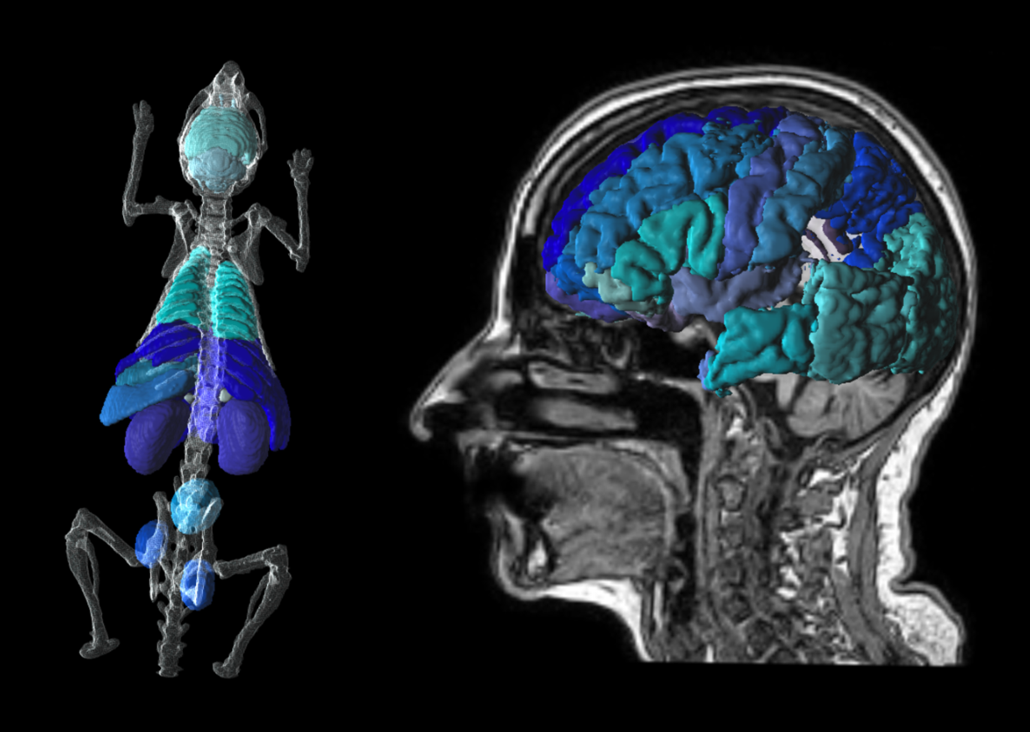

P3D Extended 3D Rendering

Translational tools to go from mouse to man. Easily transform atlases from template to individual space. Create stunning visuals for publication.